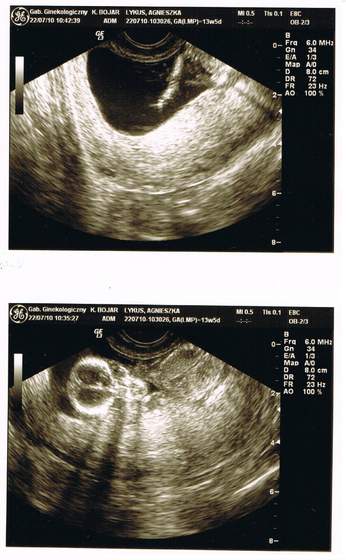

Zdjęcia naszych brzuszków i siedzących w nich maluszków - USG

A ja już po usg... wszystko mi pokazała, wytłumaczyła gdzie co jest ale nie jestem zadowolona ze zdjęć myślałam, że zrobiła calego maluszka zebym miala po zdjeciu dla jednej i drugiej babci a tu tylko głowka i rączki...

CCF20100722_00000d.jpg

Ale dzidzia mnie miło przywitała pomachała rączkami potem possała paluszka i grzecznie dała się zmierzyć ;)) Aż ryczałam jak głupia jak to zobaczyłam ! ^^